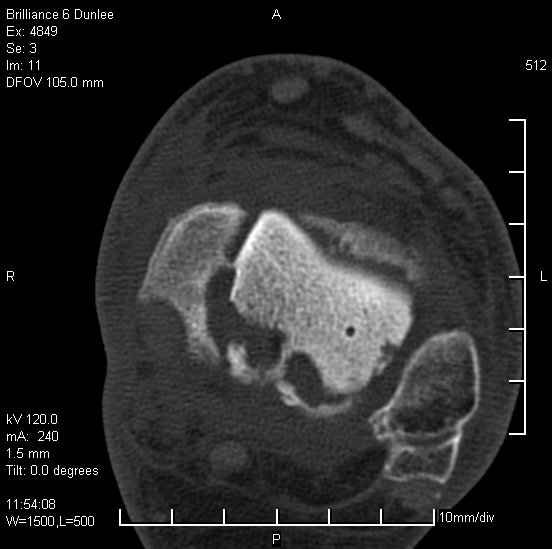

Асептический некроз таранной кости.

На лечении находится пациент 35 лет. Травма в сентябре 2008 г.- открытый вывих таранной кости

В день травмы ПХО, вправление вывиха, трансартикулярная фиксация. Рана зажила первично. С января нагрузка на конечность. С конца апреля- болевой синдром. На рентгенограммах и КТ признаки ас. некроза таранной кости, артроз подтаранного и голеностопного суставов.